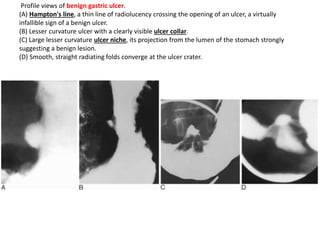

Profile views of benign gastric ulcer.

(A) Hampton's line, a thin line of radiolucency crossing the opening of an ulcer, a virtually

infallible sign of a benign ulcer.

(B) Lesser curvature ulcer with a clearly visible ulcer collar.

(C) Large lesser curvature ulcer niche, its projection from the lumen of the stomach strongly

suggesting a benign lesion.

(D) Smooth, straight radiating folds converge at the ulcer crater.